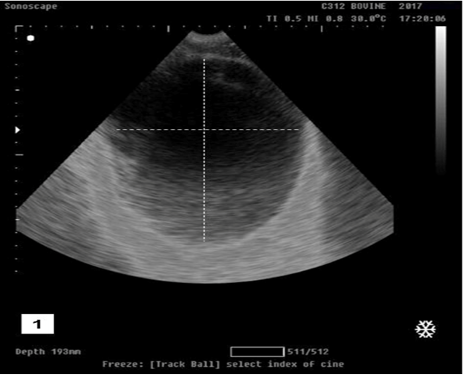

Figure 1

Ultrasonographic image showing anechoic distended round structure representing the urinary bladder with tensed wall in buffalo calf with urine retention and had intact urinary bladder.